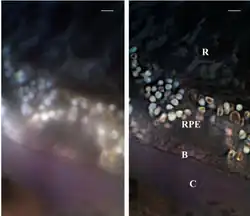

SMI can be combined with other super resolution technologies, for instance with 3D LIMON or LSI-TIRF as a total internal reflection interferometer with laterally structured illumination (this last instrument and technique is essentially a phase-shifted photon tunneling microscope, which employs a total internal reflection light microscope with phase-shifted evanescent field (Guerra, 1996).[32] This SMI technique allows one to acquire light-optical images of autofluorophore distributions in sections from human eye tissue with previously unmatched optical resolution. Use of three different excitation wavelengths (488, 568, and 647 nm), enables one to gather spectral information about the autofluorescence signal. This has been used to examine human eye tissue affected by macular degeneration.[36]